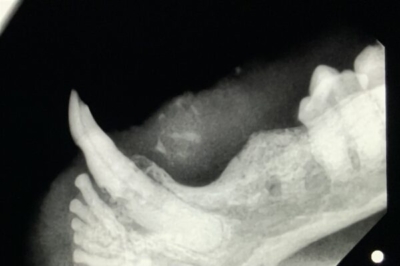

他院で抜歯したが治らないという口内炎の猫ちゃん。初日、歯科用レントゲンでなくとも麻酔をかけず一般的な頭部のレントゲン撮影でも歯の根っこが下顎に残っているのがわかった。

歯科レントゲンで下顎の画像。数本並んでいる白いのが折れて残っている歯根。これを残すと治らない。